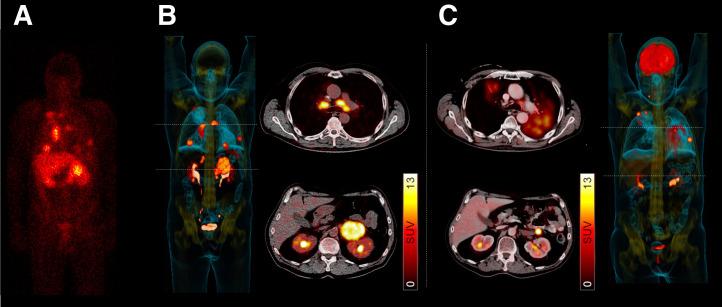

In the early 2000s, major clinical trials provided evidence of a favorable outcome from antibody-mediated radioimmunotherapy for hematologic neoplasms, which then led to Food and Drug Administration approval. For instance, the theranostic armamentarium for the referring hematooncologist now includes Y-ibritumomab tiuxetan for refractory low-grade follicular lymphoma or transformed B-cell non-Hodgkin lymphoma, as well as I-tositumomab for rituximab-refractory follicular lymphoma. Moreover, the first interim results of the SIERRA phase III trial reported beneficial effects from the use of I-anti-CD45 antibodies (Iomab-B) in refractory or relapsed acute myeloid leukemia. During the last decade, the concept of theranostics in hematooncology has been further expanded by C-X-C motif chemokine receptor 4-directed molecular imaging. Beyond improved detection rates of putative sites of disease, C-X-C motif chemokine receptor 4-directed PET/CT also selects candidates for radioligand therapy using β-emitting radioisotopes targeting the identical chemokine receptor on the lymphoma cell surface. Such image-piloted therapeutic strategies provided robust antilymphoma efficacy, along with desired eradication of the bone marrow niche, such as in patients with T- or B-cell lymphoma. As an integral part of the treatment plan, such radioligand therapy-mediated myeloablation also allows one to line up patients for stem cell transplantation, which leads to successful engraftment during the further treatment course. In this continuing education article, we provide an overview of the current advent of theranostics in hematooncology and highlight emerging clinical applications.

在 21 世纪初,几项大型临床试验为血液系统恶性肿瘤的抗体介导的放射免疫治疗提供了有利结果的证据,随后获得了食品和药物管理局的批准。例如,现在,血液肿瘤学家的治疗武器库包括用于难治性低级别滤泡淋巴瘤或转化 B 细胞非霍奇金淋巴瘤的 Y-碘替比单抗替曲膦,以及用于利妥昔单抗难治性滤泡性淋巴瘤的 I-替西莫单抗。此外,SIERRA 三期试验的首次中期结果报告了使用 I-抗-CD45 抗体(Iomab-B)治疗难治性或复发性急性髓系白血病的有益效果。在过去十年中,血液肿瘤学中的治疗学概念通过 C-X-C 基序趋化因子受体 4 定向分子成像得到了进一步扩展。除了提高潜在疾病部位的检测率外,C-X-C 基序趋化因子受体 4 定向 PET/CT 还选择了使用针对淋巴瘤细胞膜上相同趋化因子受体的 β 发射放射性同位素进行放射性配体治疗的候选者。这种基于图像的治疗策略提供了强大的抗淋巴瘤疗效,并期望消除骨髓龛,例如在 T 或 B 细胞淋巴瘤患者中。作为治疗计划的一个组成部分,这种放射性配体治疗介导的骨髓清除也允许患者进行干细胞移植,这导致在进一步的治疗过程中成功植入。在这篇继续教育文章中,我们概述了血液肿瘤学中治疗学的当前发展,并强调了新的临床应用。